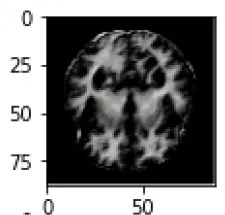

The database used in this study consists of a total of 6,200 AD images that are retrieved from the Kaggle database. It comprises grayscale images of 896 MD, 64 Mod D, 3,200 ND, and 1,966 VMD images, with a dimension of (208 × 176 × 3) pixels. The dataset for evaluation is divided in such a way that 80% of the image samples are utilized for training the model and the remaining 20% are utilized for testing the model (Filipovych et al., 2011). Figure 2 shows the database of MRI images. Table 2 shows the publicly available AD dataset.

FIGURE 2

www.frontiersin.org

Figure 2. Alzheimer's disease: (A) M.D, (B) Mod.D, (C) N.D, and (D) V.M.D.